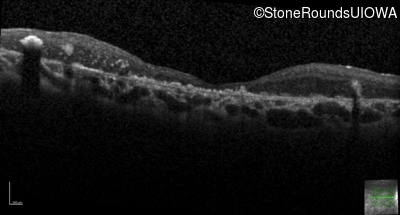

Optical Coherence Tomography - Right - 20/400 sc

Exemplar / OCT Stack

Optical Coherence Tomography - Left - 20/250 sc